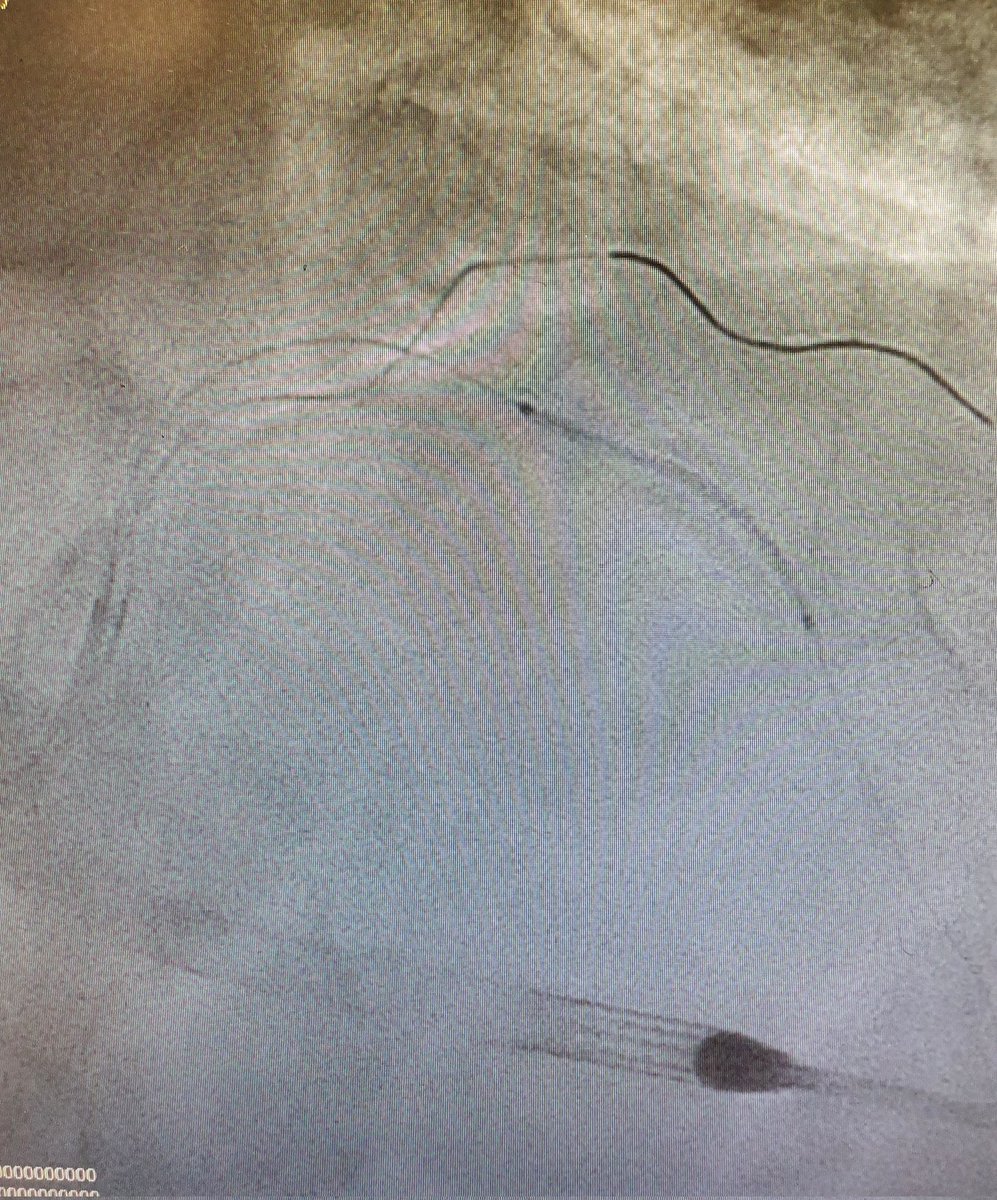

Interventional cardiologist, Lancashire Cardiac Centre, UK. Past fellow Uni of Western Ontario, Canada. Cardiology Manchester.BartsSMD.